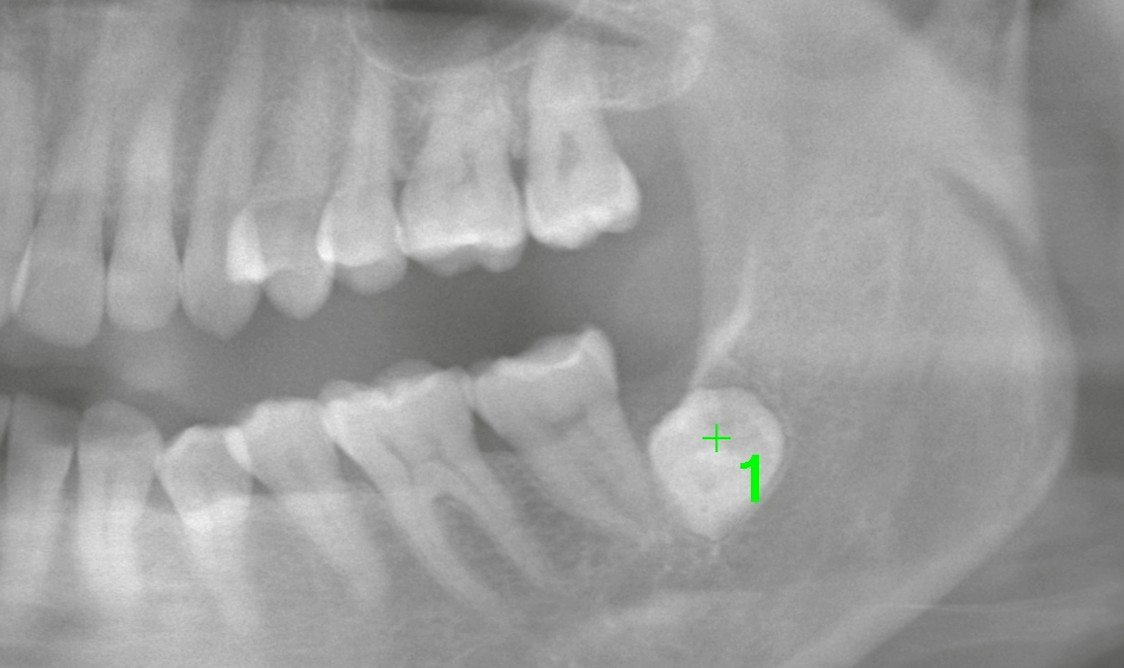

まずはパノラマレントゲンで確認すると、

歯冠(歯の頭の部分)しか写っていない状態でした。

一見すると、

* 深く埋まっている

* 動きがなさそう

* 症状も今は落ち着いている

ため、「様子見」と判断されやすいケースです。

しかし、当院では必ずCT撮影を行い三次元的に評価します。